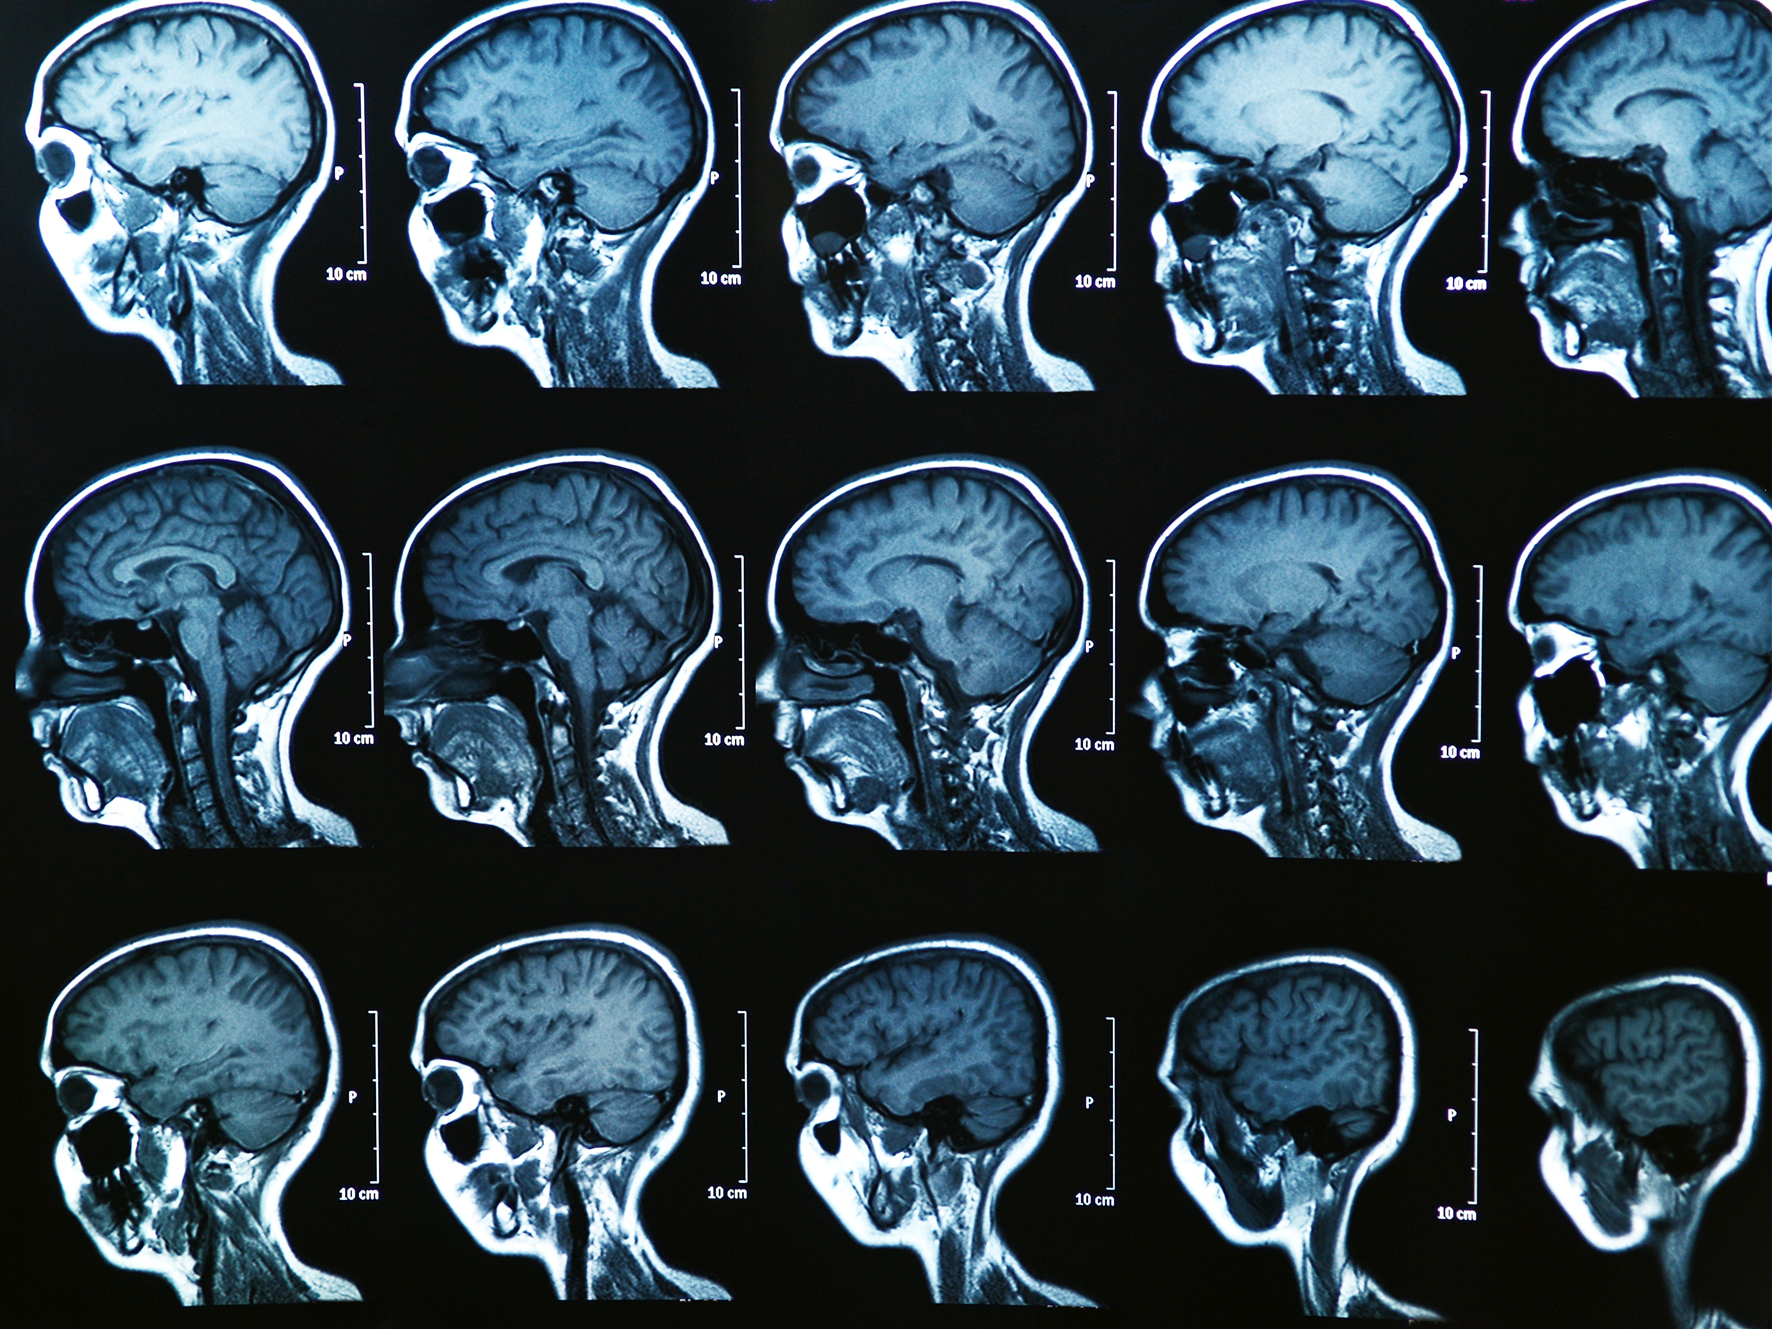

Medical imaging is an important tool for diagnosis and treatment (here: MRT image of a human brain)<address>© colourbox.de/Bunyos</address>

Medical imaging is an important tool for diagnosis and treatment (here: MRT image of a human brain)

Medical imaging makes it possible to take a look inside the human body from the outside and make hidden processes visible, which makes it important for the diagnosis and treatment of a variety of diseases. Something that is becoming increasingly important is so-called four-dimensional imaging. In this process, three-dimensional images are generated and, in addition – as a “fourth dimension” – changes that occur over time can be reconstructed and made visible. This makes it possible, for example, to record movements resulting from the heartbeat or from breathing and produce sharper images in doing so. Mathematics plays a key role in this. A new joint project being undertaken nationwide in Germany is now aiming to improve the methods of 4D-imaging – making it possible, for example, to analyse movements and simultaneously measure molecular processes quantitively. “Quantitively” in this case means, for example, that it can be measured how much sugar the cells of an organ or tissue consume in a certain period of time (glucose metabolism). The project is being coordinated by Prof. Martin Burger, a mathematician at the University of Münster.

The four-dimensional imaging process takes place using magnetic resonance imaging (MRI), for example, or positron emission tomography (PET). In these cases, signals from inside the body are measured. However, these signals are not present, initially, in the form of images. Only by using mathematical models can the three-dimensional images generated over time be reconstructed from the measurement data. “It’s a really fascinating challenge, not only to record the movements of organs or of patients during a dynamic measurement, but also to use these movements to improve the quality of the images,” says Martin Burger. “This makes it possible to see more precisely how contrast media spread out in the body.” These new methods are important for example in examinations of the cardiovascular system or of kidney functions, he adds, and the aim is that they should help in enabling physicians to make clearer assessments of functionality and to draw up more precise diagnoses of diseases. The project is being funded to the tune of 836,000 euros, for three years, by the Federal Ministry of Education and Research out of the “Mathematics for Innovations in Industry and Services” programme.